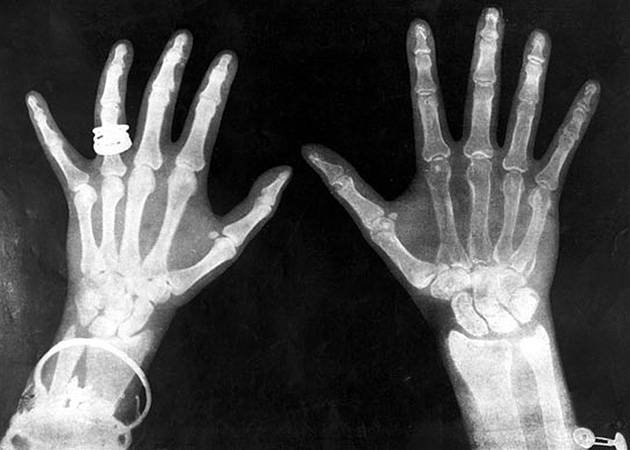

Гладкая кожаРентгеновское излучение сегодня помогает нам диагностировать заболевания, а вот сразу после изобретения рентгена излучение пытались использовать в косметических целях. Для удаления нежелательных волос. Волосы действительно выпадали, это факт. Правда, заодно истончалась кожа и появлялись морщины. Но самое страшное — спустя несколько лет стало ясно, что эффективный способ эпиляции привел к всплеску заболеваний раком.